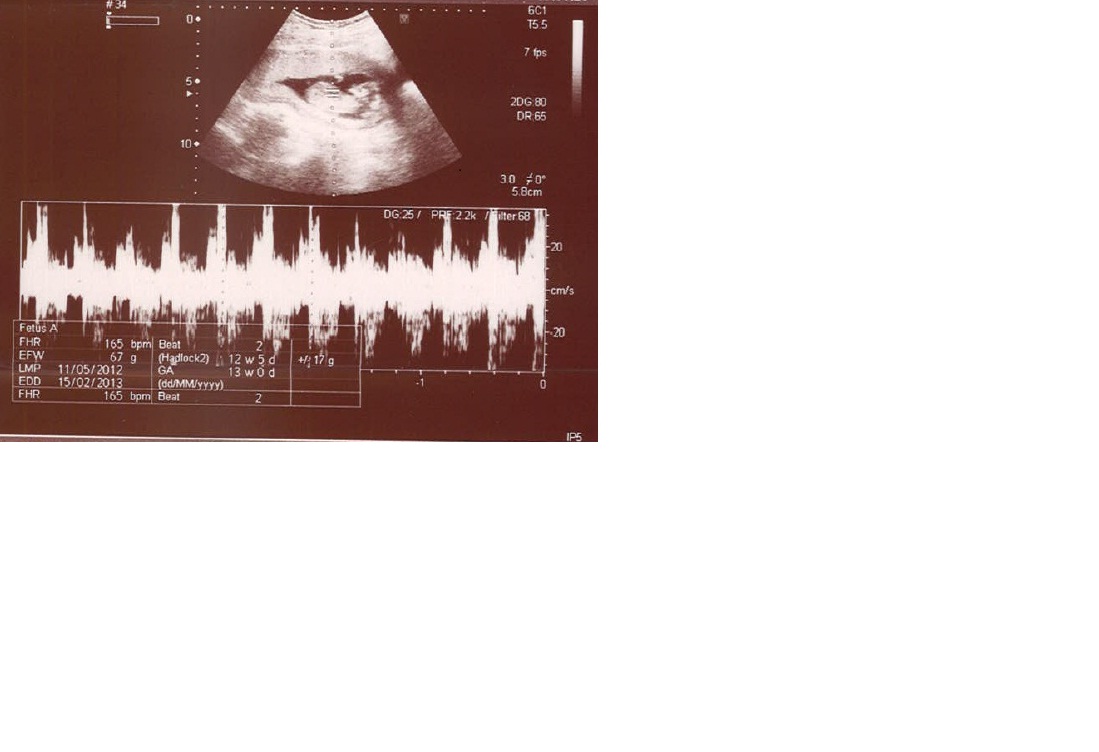

this is my 12 week ultrasound pic.